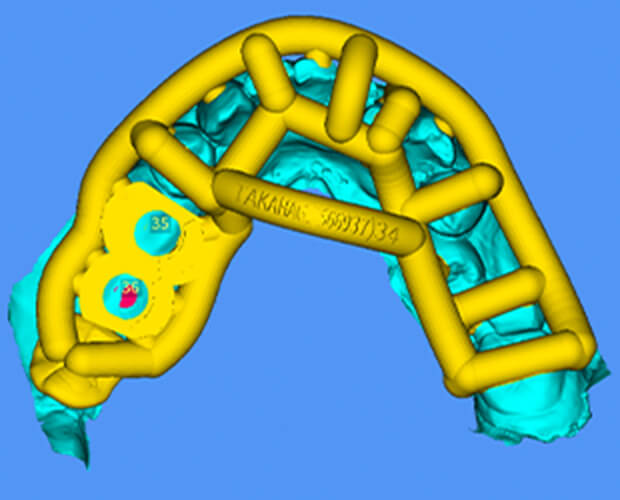

SMOP

スモップ

インプラント治療におけるコンピューターガイドシステムの一つで、CT診断によるシミュレーションを実際の口腔内で再現いたします。

これにより、より正確なインプラント埋入が可能になり、患者の負担を軽減する手術(フラップレス手術)も行える場合があります

特徴

• マッチング精度の徹底的追求

• 口腔内での適合度の追求

• さまざまな症例に対応

• 部分的骨支持にも対応可能

• インプラントシステムの多くに対応

• 複数のウィンドウ作製可能